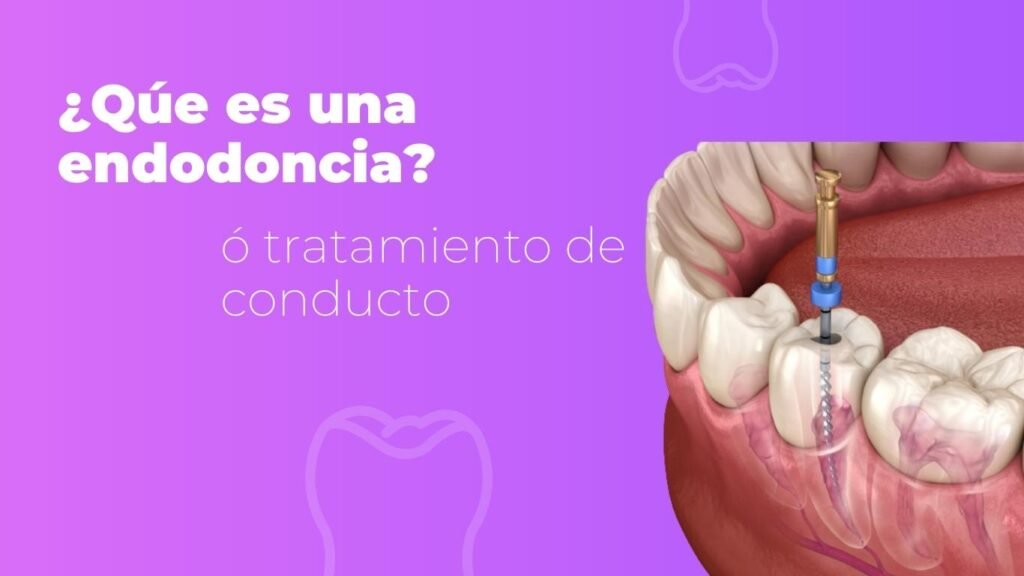

Endodoncia

Si presentas infección dental, ya sea por caries o por alguna fractura en tu diente, probablemente el paso a seguir es el tratamiento del nervio de tu diente. Con este procedimiento podemos preservar tu diente. Acude con nosotros para un diagnóstico correcto y así poder determinar si este tratamiento es una opción para ti.